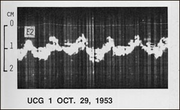

| 12:57, 25 September 2007 | FirstEchoCor.png (file) |  |

54 KB | Vdbilt | The first echocardiogram made by Inge Edler and Hellmuth Hertz in 1953 | 1 |